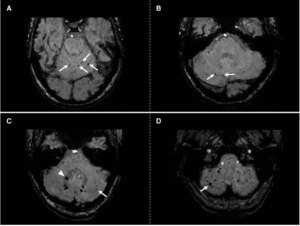

Imaging post-trattamento

L’imaging post-trattamento è una fase fondamentale del protocollo, con il triplice obiettivo di: confermare la corretta deposizione delle microsfere nel target tumorale, escludere concentrazioni anomale in sedi extraepatiche e consentire una dosimetria a posteriori per correlare la dose effettivamente erogata con la risposta clinica.

L’imaging dell’Ittrio-90 si basa sulla rilevazione di radiazioni secondarie:

- PET/CT: sfrutta la rara emissione di positroni (circa 32 per milione di decadimenti). Nonostante il basso segnale, la moderna tecnologia PET/CT, specialmente con tempo di volo (TOF), consente un’imaging quantitativo di alta qualità. Offre una risoluzione spaziale e una capacità di quantificazione superiori rispetto alla SPECT. Per ottenere immagini di buona qualità, si raccomandano tempi di acquisizione di almeno 15 minuti;

- SPECT/CT da Bremsstrahlung: rileva i fotoni di “frenamento” prodotti dall’interazione delle particelle beta con i tessuti. Sebbene sia più accessibile, la qualità dell’immagine e l’accuratezza quantitativa sono inferiori rispetto alla PET/CT.

Per microsfere con 166Ho

L’Olmio-166 permette un imaging multimodale diretto:

- SPECT/CT: la co-emissione di fotoni gamma a 81 keV consente un’acquisizione diretta della distribuzione delle microsfere. L’imaging presenta sfide tecniche, come lo scatter dei fotoni ad alta energia e il rischio di “dead time” del detector a causa dell’elevata attività iniziale. Per questo motivo, l’acquisizione è generalmente raccomandata tra 2 e 5 giorni dopo il trattamento;

- RMN: l’Olmio-166 possiede proprietà paramagnetiche che ne consentono la visualizzazione e la quantificazione tramite Risonanza Magnetica. I vantaggi includono un’alta risoluzione spaziale e l’assenza di radiazioni ionizzanti. Tuttavia, la presenza di artefatti da suscettibilità magnetica può limitarne l’applicazione in prossimità di aria o clip metalliche.